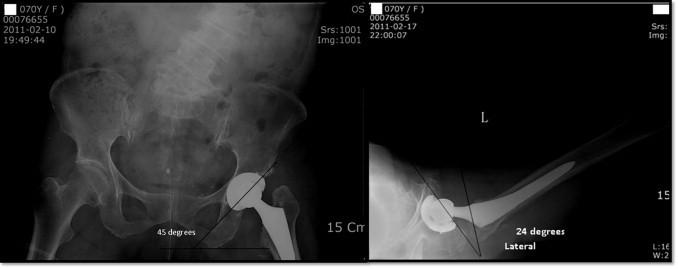

The orientation of acetabular component is influenced by pelvic tilt, body position and individual variation in pelvic parameters. Most post-operative adverse events may be attributed to malposition of the component in the functional position. There is evidence that orientation of the pelvis changes from the supine to standing position. Authors report a case of recurrent dislocation after total hip arthroplasty due to excessive pelvic tilting. PRESENTATION OF CASE A 69-year old female with coxarthrosis had undergone total hip replacement with recurrent dislocation of the hip on bearing weight in spite of using constrained acetabular component.

Our case report substantiates the influence of pelvic tilt, incurred by a sagittal deformity of spine, on dynamic orientation of the acetabular cup which was positioned in accordance with the anatomic landmarks alone. If the reference is only bony architecture and dynamic positions of the pelvis are not taken into account, improper functional orientation of the acetabular cup can result in sitting and standing positions. These can induce instability even in anatomically appropriately oriented acetabular component.

The sagittal position of pelvis is a key factor in impingement and dislocation after total hip arthroplasty. Pelvic tilting affects the position of acetabular component in the sagittal plane of the body as compared with its anatomic position in the pelvis. We suggest a preoperative lateral view of spine-pelvis, in upright and supine position for evaluation of a corrective adaptation of the acetabular cup accordingly with pelvic balance.

髋臼假体的方向受骨盆倾斜、身体位置及骨盆参数个体差异的影响。大多数术后不良事件可能归因于假体在功能位置的放置不当。有证据表明,骨盆方向从仰卧位到站立位会发生变化。作者报告了一例因骨盆过度倾斜导致全髋关节置换术后复发性脱位的病例。

一名69岁患有髋关节炎的女性接受了全髋关节置换术,尽管使用了限制性髋臼假体,但在负重时仍出现髋关节复发性脱位。

我们的病例报告证实了脊柱矢状面畸形引起的骨盆倾斜对仅根据解剖标志定位的髋臼杯动态方向的影响。如果仅以骨骼结构为参考而不考虑骨盆的动态位置,髋臼杯功能方向不当会导致坐姿和站姿问题。即使髋臼假体在解剖学上方向正确,这些情况也会导致不稳定。

骨盆的矢状位是全髋关节置换术后撞击和脱位的关键因素。与髋臼假体在骨盆中的解剖位置相比,骨盆倾斜会影响其在身体矢状面的位置。我们建议术前拍摄脊柱-骨盆的侧位片,包括直立位和仰卧位,以评估髋臼杯根据骨盆平衡进行的矫正适应性。